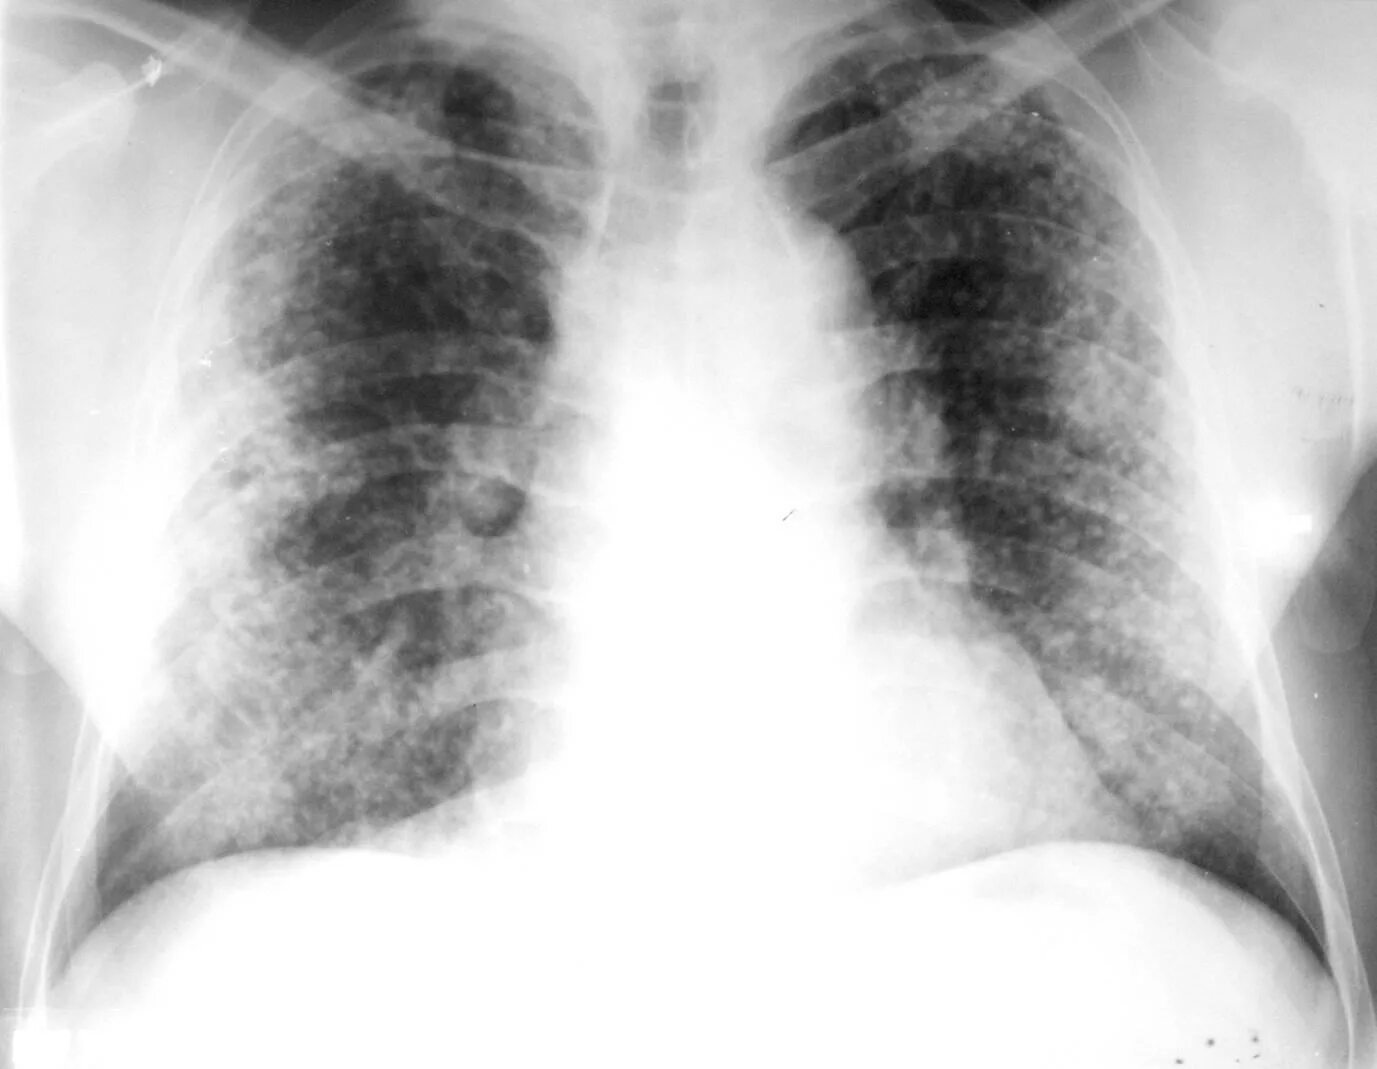

Диссеминированный туберкулез фаза инфильтрации